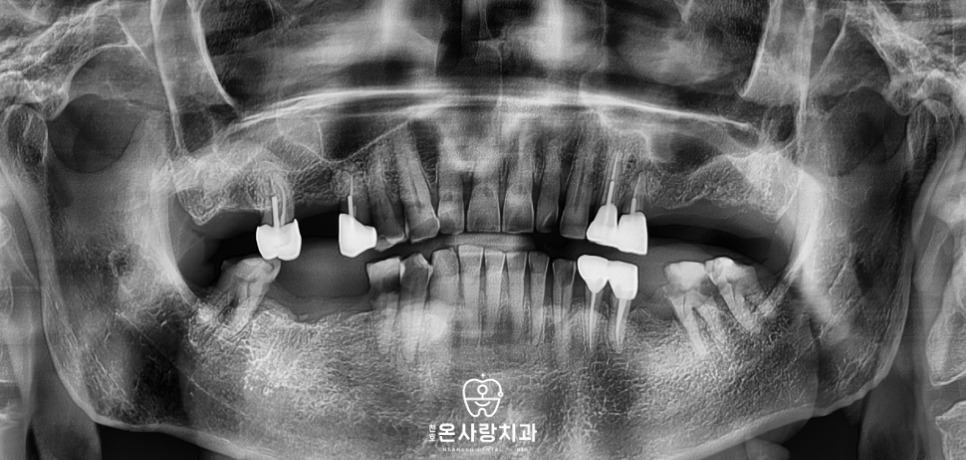

따라서 하악의 가장 뒤쪽 어금니인 부위는

치료 범위에서 제외하기로 하였습니다.

대신 그 앞 단계인 6번 치아

즉, 제1대구치까지만 구치부 보철물을 제작하여

하악의 전체적인 저작 기능을

완성하는 방향으로 계획을 수립하였습니다.

경제적인 효율성을 위해 치료 범위를

첫 번째 어금니까지로 한정하였지만

보철물 자체의 강도와 내구성은 최대로 확보하여

오랫동안 튼튼하게 사용하실 수 있도록

세심하게 제작을 진행하였습니다.